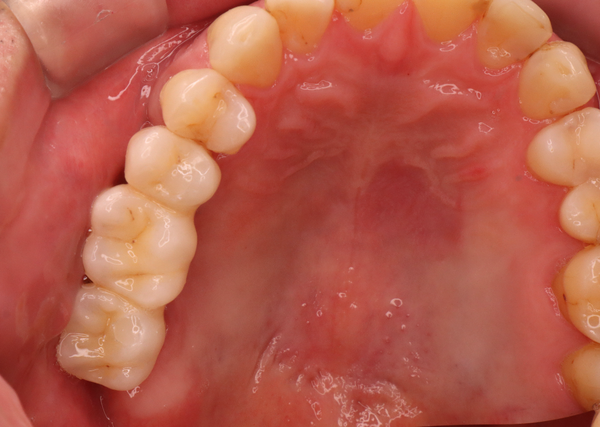

歯を抜いて放置をしていたので、そろそろ歯を入れたい、噛める様にしたい

治療方法

CTによる審査診断をした後、インプラントを入れて、2ヶ月の治癒期間を経て、セラミック補綴をしました

治療期間 3ヶ月

費用 インプラント、セラミックの被せ物 合計420,000円

治療によるリスク インプラントは歯周病に弱いため、歯周病にかかると悪化する可能性があります